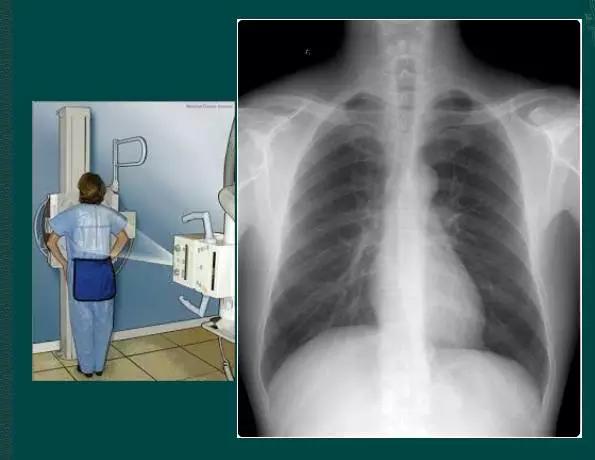

1、胸部正位片

临床拍标准的胸部正位片其实是后前位片,如上图

正常胸部后前位片